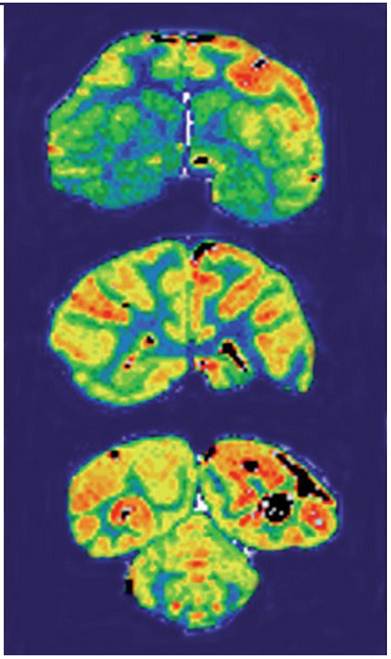

Figure 4

Film autoradiography of Rhesus monkey brain removed 2 h after an intravenous administration of [125I]-humanized HIRMAb. Coronal sections through the forebrain (top panel), midbrain (middle panel), and hindbrain/cerebellum (bottom panel) are shown. Adapted from [111].

Theranostics Image